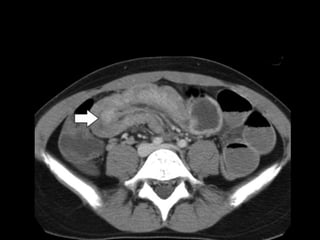

U/S

• Target sign: